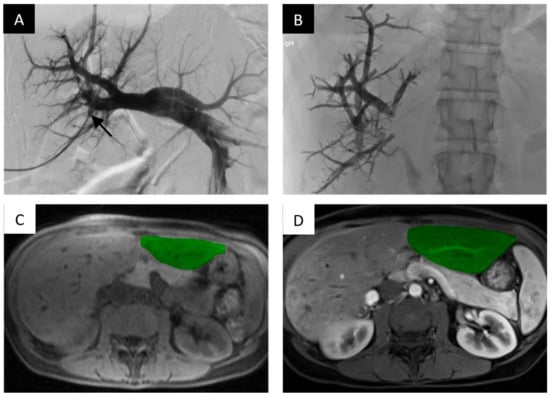

nBCA glue is a liquid embolic agent that has been shown to be effective for PVE and is commercially available in small aliquots (typically 1 mL vials). The embolic agent polymerizes when it comes into contact with an ionic agent and forms a permanent bond to adjacent structures. Typically, the agent is diluted with lipiodol which slows polymerization and allows the embolic agent to be radio-opaque on fluoroscopy (Figure 2).

Portal vein embolization of the right portal vein branch with nBCA glue and lipiodol demonstrates FLR hypertrophy. PVE of the right intrahepatic portal vein with nBCA glue with lipiodol. (A) Digital subtraction portography via side hole catheter in the main portal vein. Access gained into the portal system via anterior right portal vein branch (black arrow). (B) Final image, post-embolization of the right portal vein branches filled with radio-opaque nBCA glue. (C) Axial T1-weighted non-contrast magnetic resonance imaging (MRI) slice at the level of the hepatic parenchyma demonstrating the pre-embolized liver, with the non-hypertrophied left lobe highlighted. (D) Post-contrast axial T1 weighted MRI slice demonstrating noticeable hypertrophy of the left liver 45 days after embolization.

The ideal ratio of nBCA to lipiodol is not established but depends on how distal embolization needs to be achieved; ratios between 1:5 and 1:9 are used and administered in small 0.5 to 1.0 mL aliquots until stasis is achieved. When the portal embolization is complete, the punctured branch can be clotted off with either administration of additional nBCA and lipiodol or with manual compression while removing the access sheath. nBCA glue results in significant peripheral inflammation and produces effective portal occlusion.

Mukund et al. assessed PVE with nBCA glue and lipiodol in 28 patients [39]. The mean absolute FLR volume increased from 371 mL ± 87 to 567 mL ± 142, with a mean percentage increase of 52% ± 32 (p <0.0001). A total of 18 of the 28 patients (64.28%) underwent successful surgical resection 4–8 weeks post-PVE. Of the patients who underwent surgical resection, only one developed transient post-operative hepatic failure on post-operative day 5 but ultimately recovered on post-operative day 10.